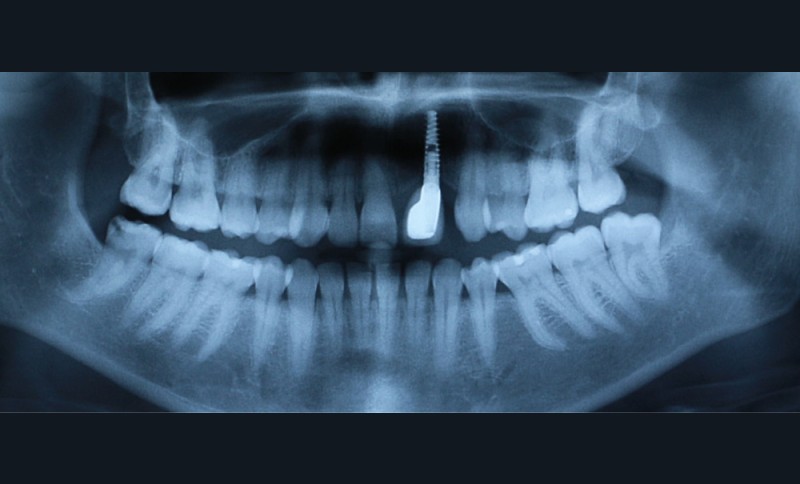

À la suite d’un accident de la voie publique il y a plusieurs années, le secteur antérieur maxillaire a été traumatisé, 21 et 22 ont été expulsées, et 11 et 12 présentent d’importantes résorptions radiculaires externes inflammatoires visibles à la radiographie panoramique (fig. 1).

Pauline a déjà eu un traitement d’orthodontie à l’adolescence, avec extraction de 25, 35, 45.

- au niveau dentaire : une arcade maxillaire asymétrique avec déviation du milieu maxillaire à gauche. On note l’absence de 21, 22, 25, 35 et 45, une classe II droite et gauche avec infraclusion antérieure et la présence d’un implant en place de 21 avec un diastème de 3 mm entre 21 et 23 (fig. 3) ;